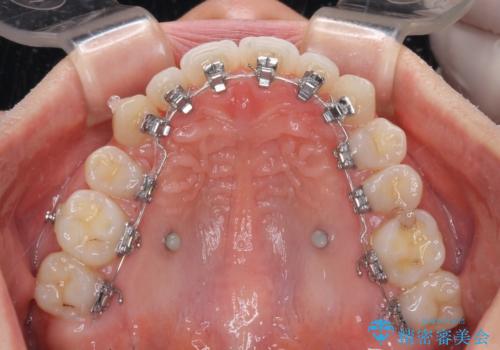

- ハーフリンガル

- 前歯のデコボコや八重歯、舌癖による開咬を気にして来院された患者様です。

目立たない装置を希望されたので、上顎が裏側装置のハーフリンガルを選択し、上顎小臼歯1本を抜歯して、補助装置を併用して矯正治療を行うこととしました。

補助装置を事前に使用したことで、あっという間に八重歯が改善し、ハーフリンガルにしては1年半もかからずに治療を終えることができました。